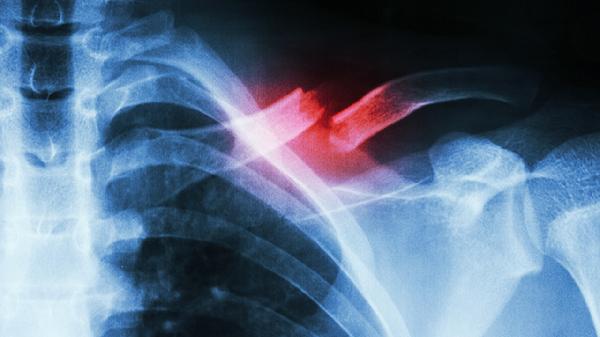

4、诊断方法:

痛风需通过血尿酸检测、关节液穿刺发现尿酸盐结晶确诊。髌骨软化依赖膝关节MRI或关节镜检查,可见髌骨软骨面毛糙、龟裂等退变表现。